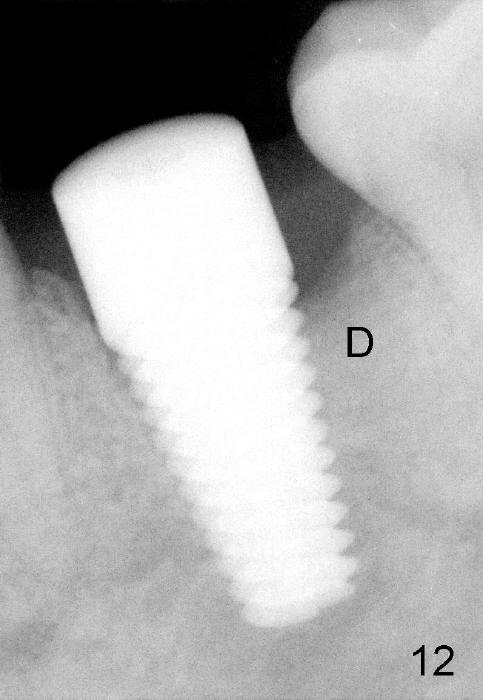

When 7x17 mm tap is placed, it drops mainly into the mesial socket (Fig.8). The septum appears to have been pushed to the distal one (<). When the 7x17 mm implant is placed with primary stability, the top portion is in the middle of the edentulous space (Fig.9). Sutures are placed mesial and distal to close the socket (Fig.10). The wound heals normally 3 months postop (Fig.11: ^). There is no bone resorption; the bone density on the top of the distal socket increases (Fig.12: D). The crown is fabricated 1 month later.